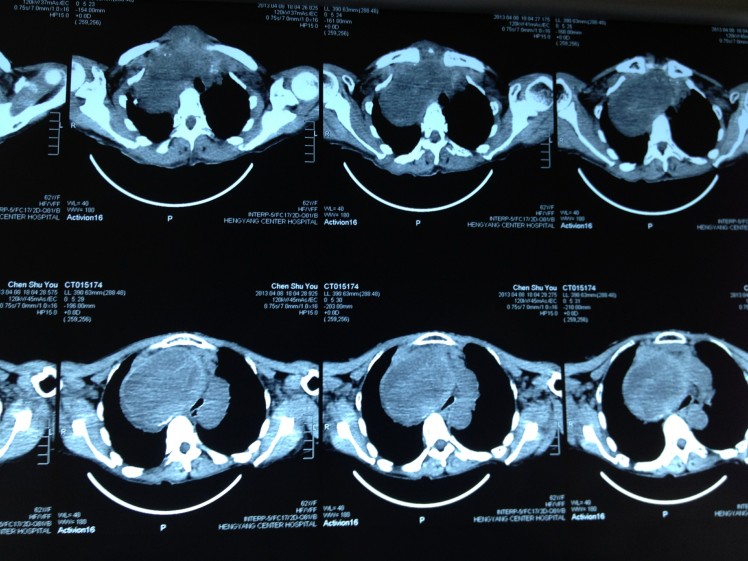

4月8日,62歲的陳阿婆因呼吸困難在家中險些窒息而被家人背送我院乳甲外科就診。陳阿婆發(fā)現(xiàn)頸部雙側(cè)腫塊已有30余年,曾就診于省內(nèi)多家大型醫(yī)院,大多專家建議開胸手術(shù),手術(shù)費高達(dá)10余萬元,有些醫(yī)院甚至考慮手術(shù)難度大、風(fēng)險高就干脆拒收入院。我院乳甲外科尹軍主任將患者收住院后,會同醫(yī)務(wù)部組織了麻醉科、放射科、胸外科、呼吸內(nèi)科、心內(nèi)科的專家會診,進(jìn)行術(shù)前討論,制定了周密的手術(shù)方案。

手術(shù)當(dāng)日,尹軍主任采用沿頸部橫紋作一橫切口,分離左右舌骨下肌瓣,在保留左側(cè)甲狀腺上極一塊如蠶豆大小的正常甲狀腺組織后,對其余雙側(cè)病變部分采取切除、止血、從胸骨下方慢慢剝離的方式,最終成功將巨大甲狀腺腫瘤切除,并將軟化氣管懸吊。整個手術(shù)過程耗時三小時,術(shù)中未輸血,整個甲狀旁腺、喉返神經(jīng)保護(hù)良好。術(shù)后病人恢復(fù)好,無相關(guān)并發(fā)癥,手術(shù)后7日患者康復(fù)出院。